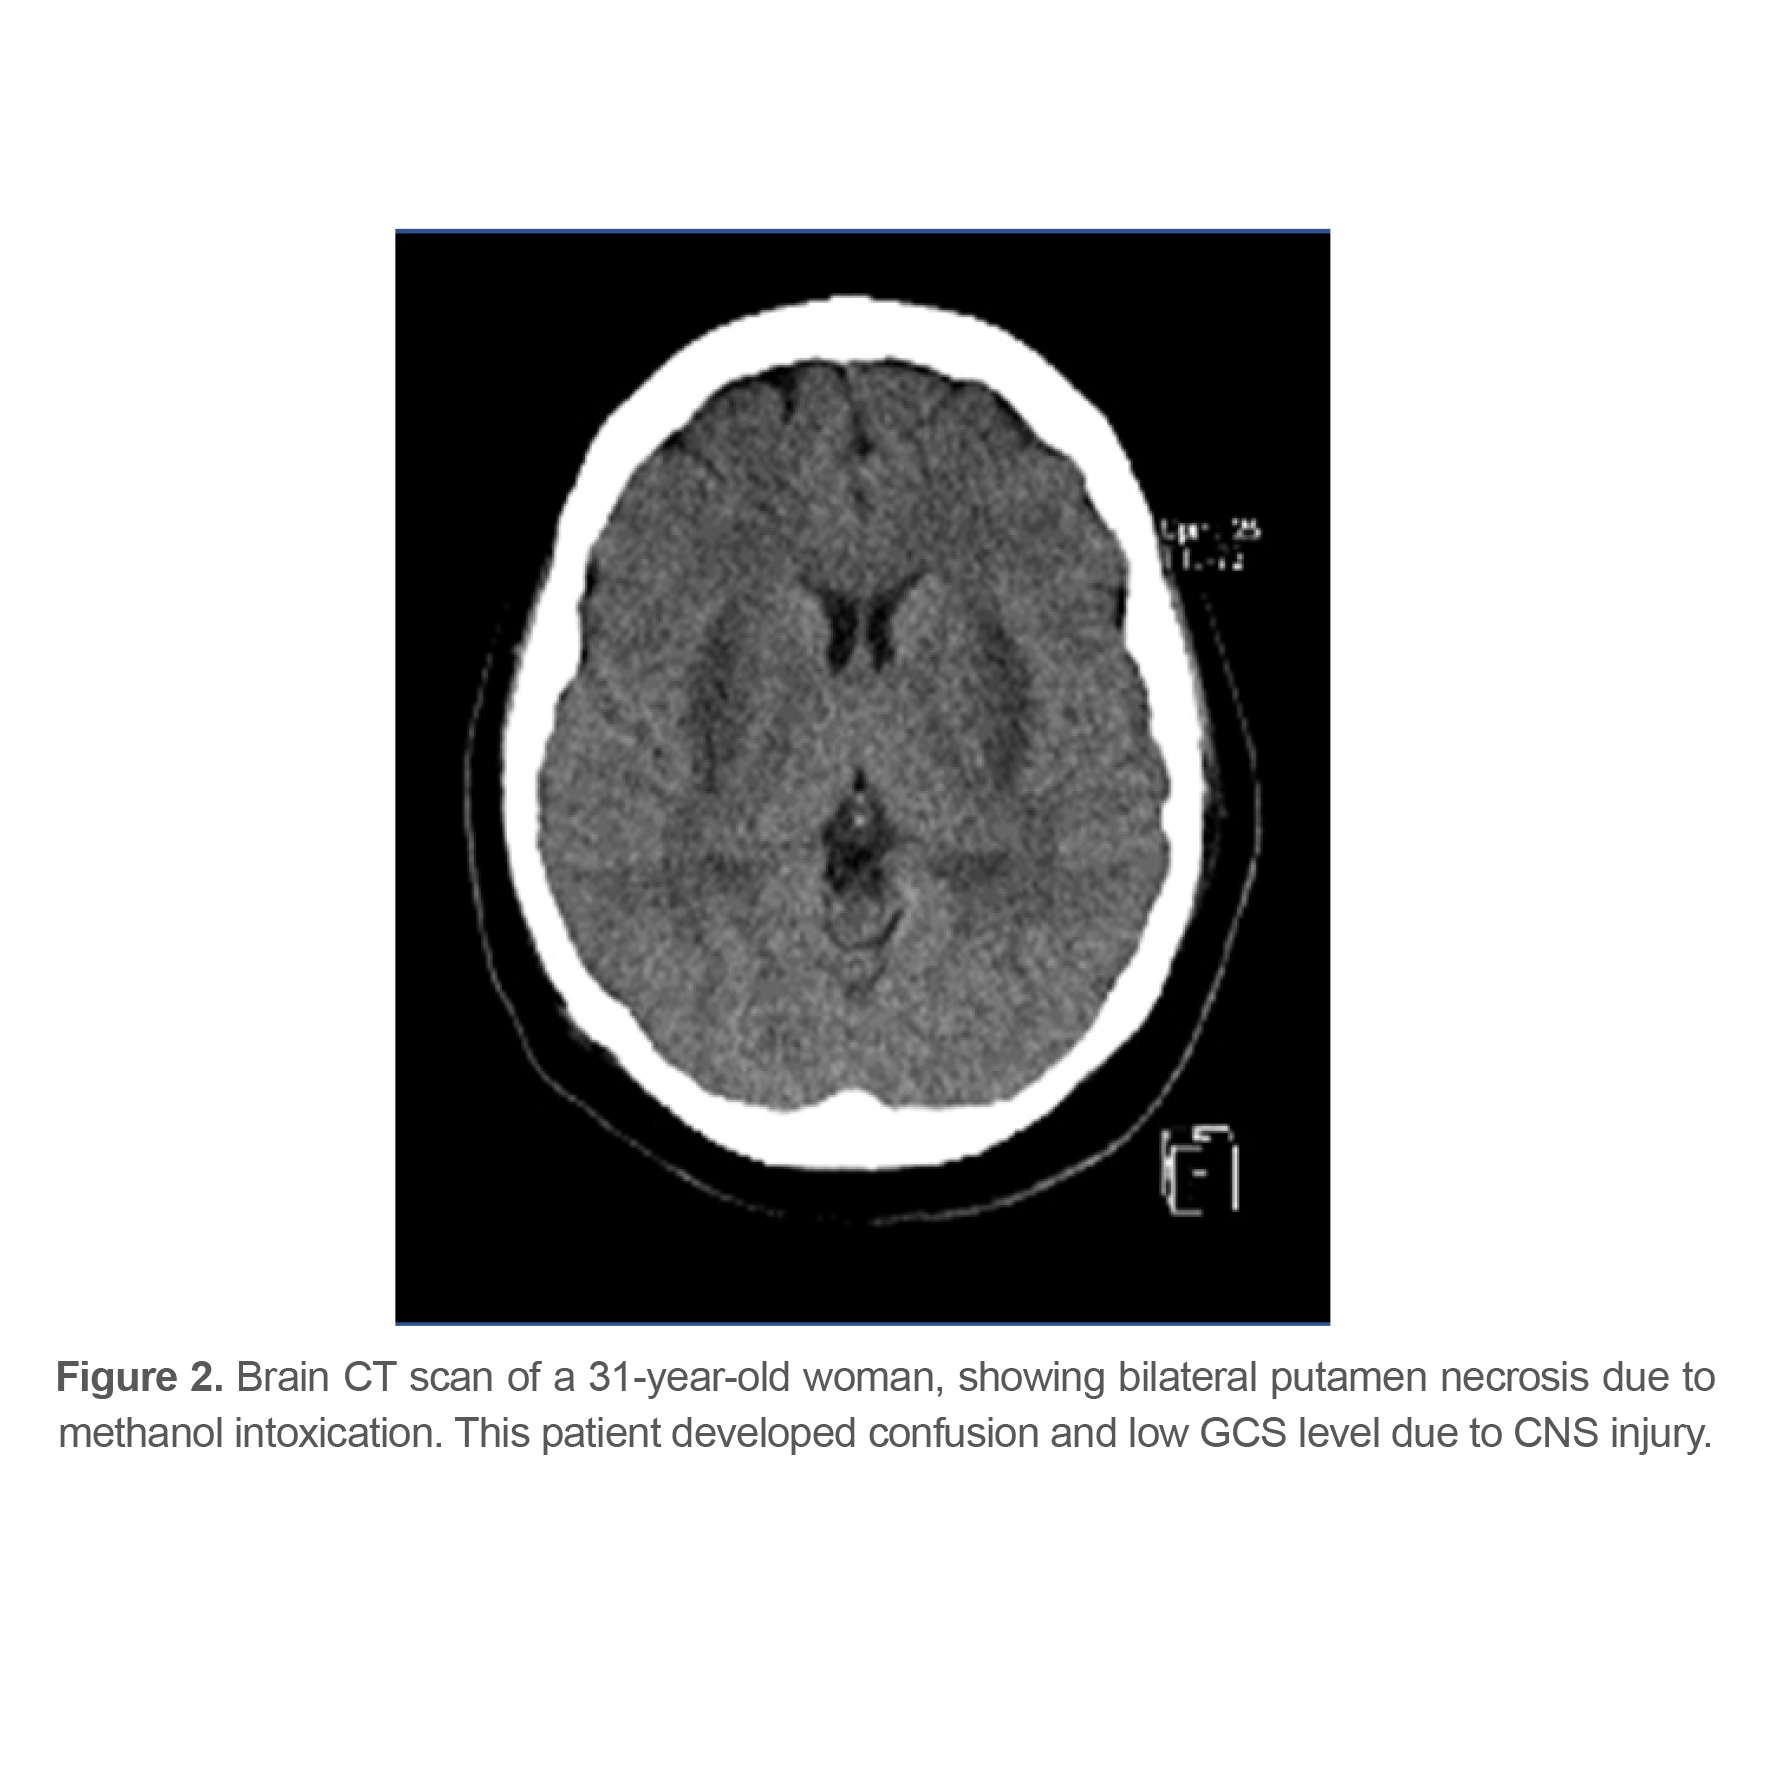

At last, 143 patients (77.72%) recovered completely, 27 patients (14.67%) had sequels at time of discharge from hospital and 14 patients (7.61%) died from methanol poisoning. Different types of complications and their frequency are listed in table 3. 21 patients (11.4%) had some sort of ophthalmologic complications at the time of discharge indicating that ophthalmologic complications were the most common complication among survivors. Figures 1-4 show brain CT scan of 4 patients with brain complications.

Figure 2. Brain CT scan of a 31-year-old woman, showing bilateral putamen necrosis due to methanol intoxication. This patient developed confusion and low GCS level due to CNS injury.